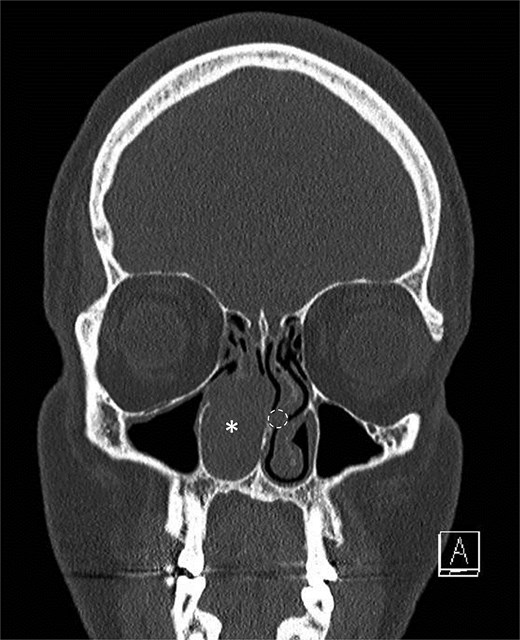

A middle-aged patient presented with progressive right nasal airway obstruction. The patient had a history of sarcoidosis, managed with fluticasone/salmeterol. CT scan revealed an expansile soft tissue mass causing complete blockage of the right nasal passage (Fig. 1). Functional endoscopic sinus surgery (FESS) was performed to remove the mass. The mass was well localized to the lower two-thirds of the middle turbinate. It was entirely separated from the nasal floor and nasal septum. A subtotal middle turbinectomy and complete FESS were performed to obtain lateral margins. Intraoperatively, a smaller second irregular focus of tissue was noted in the left nasal passage in the left middle turbinate (Fig. 1), suggesting another tumor, and was removed during a second procedure.

Initial scan demonstrating a mass. Coronal CT scan displaying expansile lesion in the right nasal passage denoted by asterisk. Lesion was noted to have erosion of distal nasolacrimal duct and inferior turbinate without bony erosion. Location of lesion in left nasal passage denoted by dotted circle.